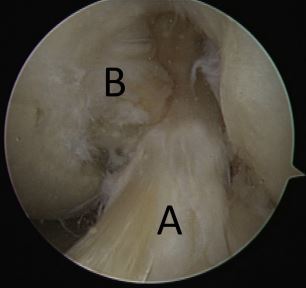

what might you find in the intercondylar notch?

A

loose bodies

trochlear chondromalacia

ACL tear

PCL tear